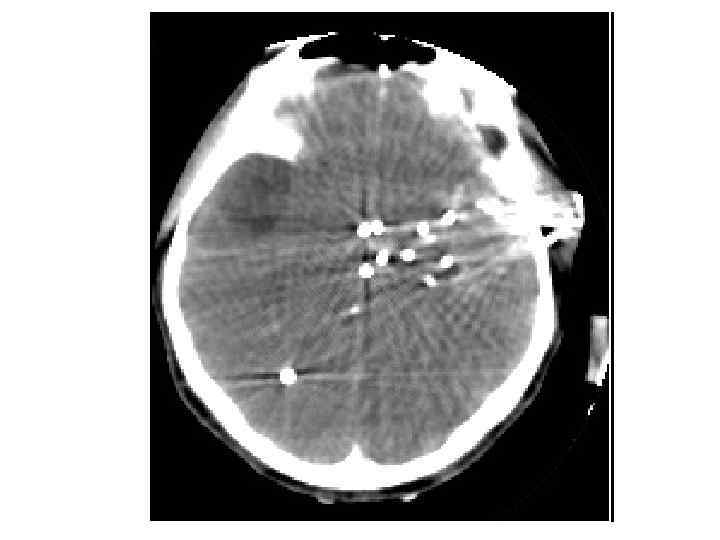

Пулевые ранения

Дробовое ранение

Дополнительная классификация огнестрельных ранений Сквозное ранение (имеется входное и выходное отверстия. Пуля не остаётся в организме) n Слепое ранение (имеется только входное отверстие. Пуля остаётся в организме в конце раневого канала) n Касательное (направлено тангенциально к поверхности тела. Раневой канал имеет форму жёлоба) n

Отличительные особенности огнестрельных ран n n Наличие зоны мертвых тканей вокруг раневого канала (первичный некроз); Неравномерная протяжённость и направление раневого канала. Большое выходное отверстие при его наличии; Наличие в ране инородных частиц, втянутых внутрь большой скоростью ранящего снаряда; Образование в последующие часы и дни после ранения, новых очагов отмирающих тканей, в области значительно большей области раневого канала (вторичный некроз).